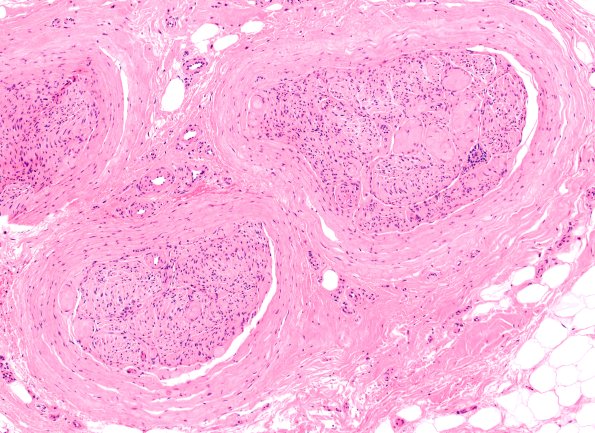

Washington University Experience | PERIPHERAL NEUROPATHY | 19 TRAUMATIC INJURIES | 22A2 Median nerve compression (Case 22) H&E 10X 3

22A2-4 There is marked expansion and fibrosis of the perineurium. In addition, there are numerous atypical Renaut bodies which appear more fibrotic than the typical wispy constructs seen in most cases in which they are encountered. Since Renaut bodies are often described to result from chronic compression the clinical scenario appears particularly valid in this case. Some vessels also appear thickened but there is no evidence of angionecrosis.